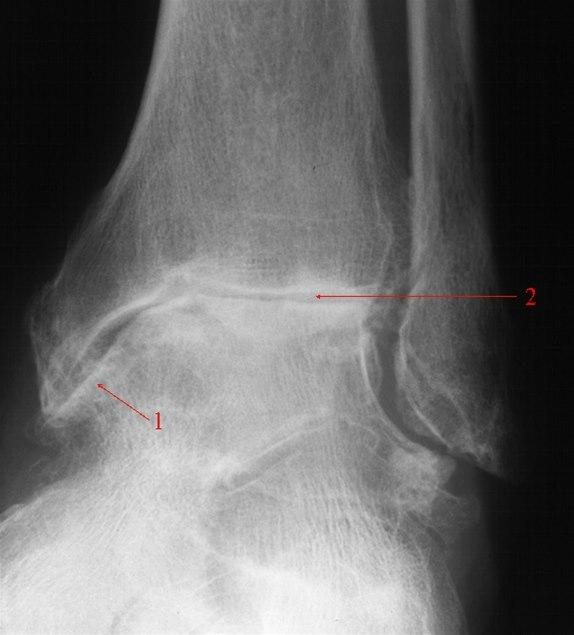

Forkalkninger og redusert leddspalte.Plagene er typiske. Kombinert med vanlig legeundersøkelse av ankelen kan diagnosen være sannsynlig uten andre undersøkelser. Sikker diagnose fås ved røntgenundersøkelse som viser nedslitt brusk og eventuelt forandringer i selve beinstrukturen.